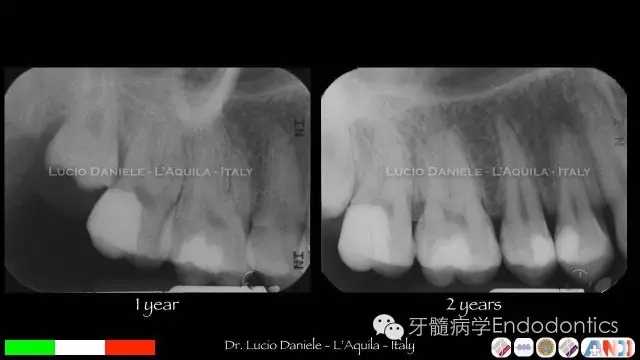

圖7.隨訪1年、2年